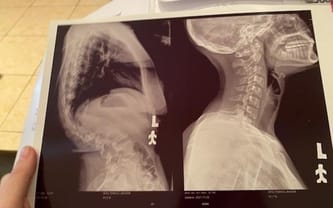

Jagoda zaledwie pół roku temu skończyła 16 lat, przed nią powinno być całe życie, tymczasem mija w strachu... Toczy się w cieniu strasznej choroby! Skolioza wykrzywia kręgosłup, prowadząc do ucisku na rdzeń... Jeśli nic nie zrobimy, Jagodzie grozi całkowity paraliż! Operacja jest jedynym ratunkiem - musi odbyć się jak najszybciej, dlatego prosimy o pomoc!

Skolioza to choroba, prowadząca do choroby kręgosłupa. Metod leczenia i pomocy szukamy właściwie od zawsze. Próbowaliśmy wszystkiego... Ćwiczenia, rehabilitacja, gorsety. Bezskutecznie... Lekarze rozłożyli ręce. Mówią, że jedyną nadzieją na uratowanie kręgosłupa Jagody jest skomplikowana, wieloetapowa operacja.

Niedawno znów wróciliśmy ze szpitala... Jagoda zaczęła czuć mrowienie w nogach, była bardzo słaba. Z przerażeniem obserwuję, jak nogi coraz częściej odmawiają jej posłuszeństwa. Córka uskarża się też na ból. Ucisk na rdzeń kręgowy, jakiego dokonuje krzywy kręgosłup, jest już coraz większy... Trzeba działać pilnie. Ta zbiórka to wyścig z czasem... Jeśli dojdzie do paraliżu, jest on nieodwracalny. Bez operacji nastąpi prędzej czy później...